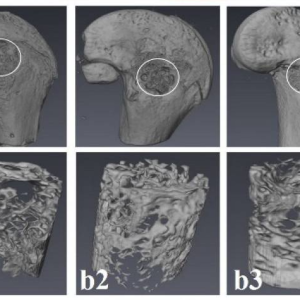

بازسازی نقایص استخوانی در مدل استئونکروز فمور خرگوش با استفاده از داربستهای کامپوزیت پلی (اپسیلون-کاپرولاکتون)/نانوذرات ویلمایت

نویسندگان: لطیفه کریمزاده باردیی، احسان سیدجعفری، قمرتاج حسین، محمد نبیونی، محمد حسین مجلس آرا و Jochen Salber چکیده:استئونکروز مرتبط با استروئید (SAON)[1] یک بیماری مزمن است